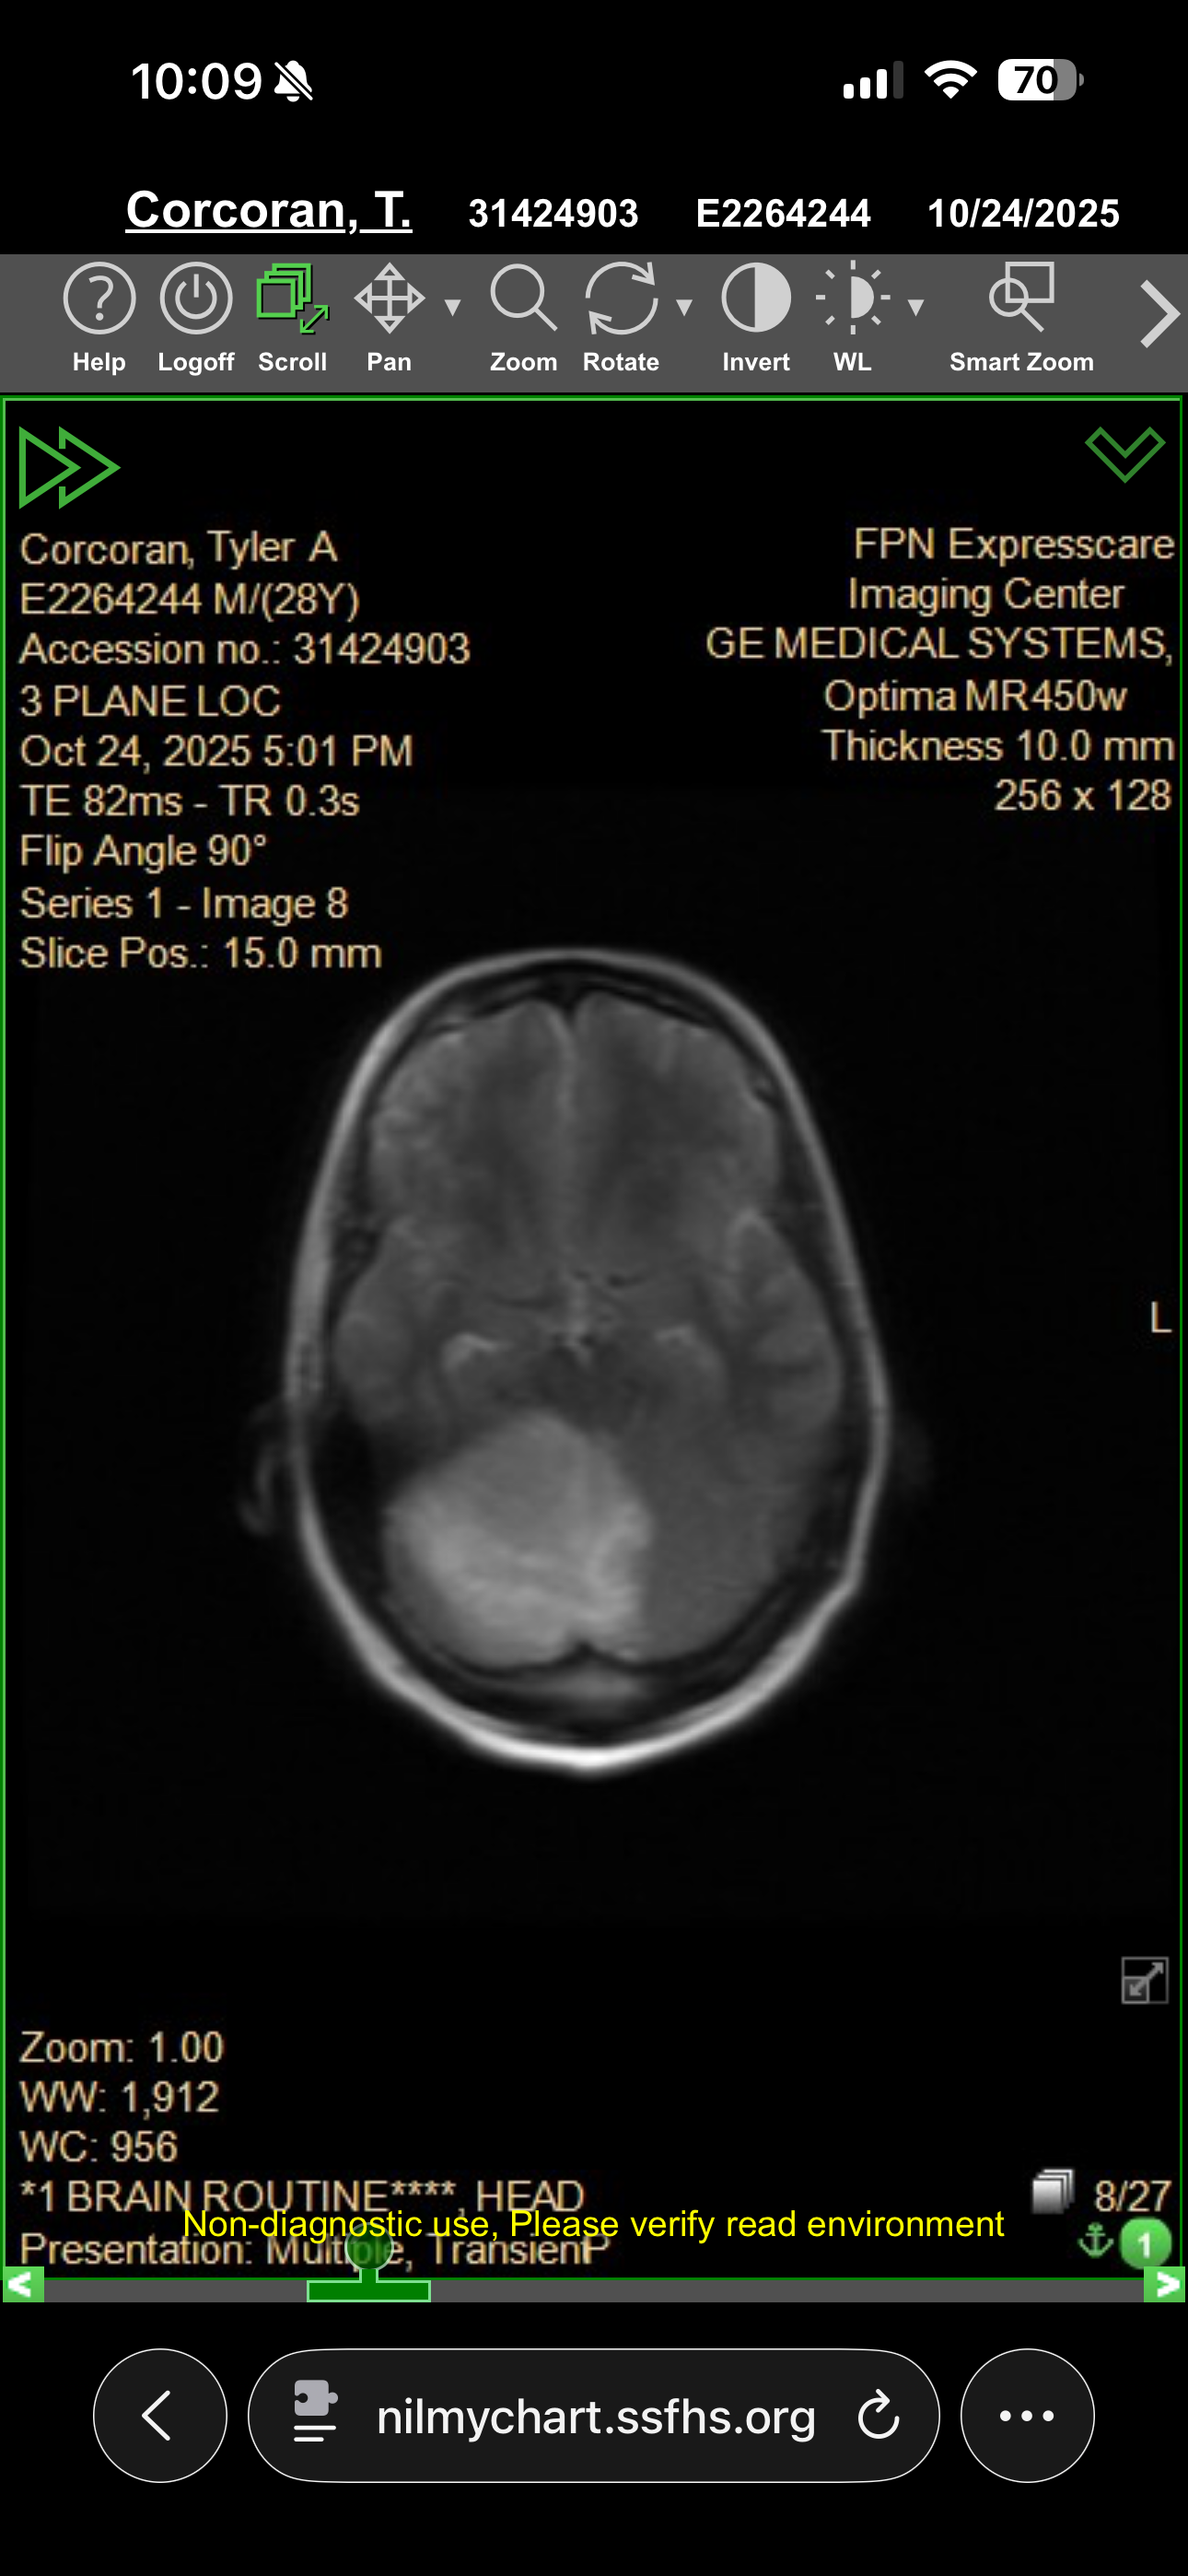

Hello, my name is Lauren. The man in the photos is my wonderful husband Tyler. In March of 2024, he discovered that he had a brain tumor in his cerebellum, leading to a decline in his motor skills, including his balance and ability to walk. Over time his symptoms have continued to worsen, the tumor has grown, and he has become a shell of the man I once knew. At the beginning of November 2025, it all came to a head when we had to rush him to the emergency room for life threatening symptoms which led to him having brain surgery on November 7th. The road to recovery is a long one, and we are just at the start. He is an amazing man and a devoted father to our 2 year old daughter. With this serious of a condition, he is unable to work and I have had to reduce my hours working to help him at home. Any help to keep us afloat through all of the medical expenses and living expenses during this difficult time is greatly appreciated. Thank you for taking the time to read Tyler’s story.